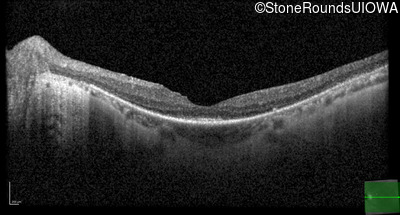

Optical Coherence Tomography - Left - 20/20 -2

Exemplar / OCT Stack